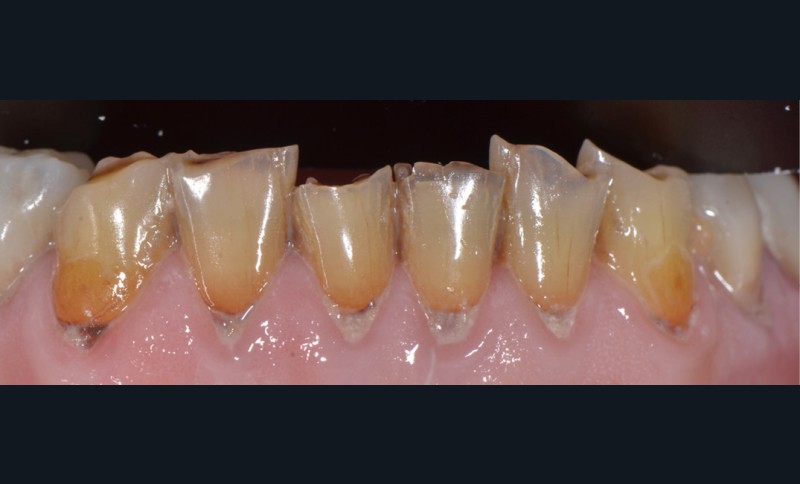

Prenons les lésions cervicales non carieuses, exemple typique de zone de dentine sclérotique (fig. 3) :

– la couche hyperminéralisée est épaisse dans la partie la plus profonde de la lésion. Elle présente deux espèces de bactéries : l’une piégée dans la partie minérale, l’autre se développant en tapis filamenteux à sa surface ;

– dans la partie occlusale de la lésion, la couche hyperminéralisée ainsi que la couche bactérienne de surface sont plus fines ;

– dans la partie gingivale de la lésion, la couche hyperminéralisée est encore plus fine (moins de 1 micron) et exempte de toute bactérie.